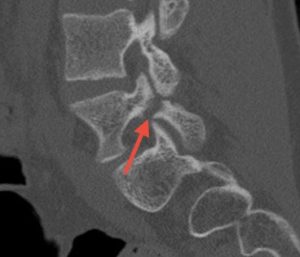

FM: Pars fracture repair is a very exciting area in spine surgery, particularly for younger patients and athletes, because it offers the ability to treat the source of pain while preserving motion. My focus has been on applying robotic technology to direct pars repair in carefully selected patients. As the highest-volume surgeon in New Jersey performing outpatient robotic pars repairs, I am currently studying my outcomes. We’re seeing that robotics can transform what was traditionally a more invasive procedure—often requiring 1-2 night hospital stays—into an outpatient surgery using small percutaneous incisions.

Patients are returning to sports as early as six to eight weeks post-operatively. While long-term comparative data is still evolving, robotics may improve reproducibility, shorten recovery, and maintain similar healing rates and long-term outcomes compared to traditional open techniques.

Images show pre-op CT and post-op CT, showing the healing, as well as a picture of the incisions. Image credits: Dr. Farah Musharbash